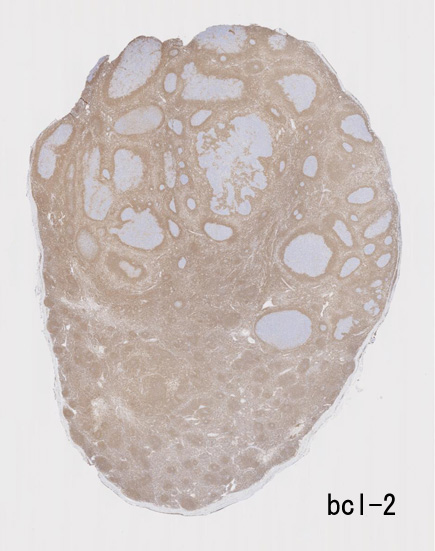

大きな胚中心を持つ多数のリンパ濾胞が見られる。胚中心の辺縁は不明瞭でマントル層も薄くなっている。1カ所マントル層リンパ球の侵入によりバラバラになった巨大な胚中心が認められ, macrofollicular patternと記載されるPTGCです。

鑑別にあがるfollicular lymphoma floral variantは全ての濾胞が腫瘍性であり, 本性例では除外可能と考える。

Diagnosis: Reactive lymphadenitis with PTGC